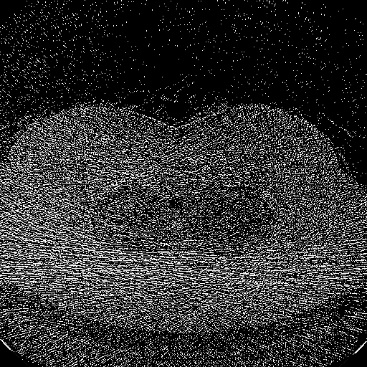

Low-Dose Computed Tomography (LDCT) technique, which reduces the radiation harm to human bodies, is now attracting increasing interest in the medical imaging field. As the image quality is degraded by low dose radiation, LDCT exams require specialized reconstruction methods or denoising algorithms. However, most of the recent effective methods overlook the inner-structure of the original projection data (sinogram) which limits their denoising ability. The inner-structure of the sinogram represents special characteristics of the data in the sinogram domain. By maintaining this structure while denoising, the noise can be obviously restrained. Therefore, we propose an LDCT denoising network namely Sinogram Inner-Structure Transformer (SIST) to reduce the noise by utilizing the inner-structure in the sinogram domain. Specifically, we study the CT imaging mechanism and statistical characteristics of sinogram to design the sinogram inner-structure loss including the global and local inner-structure for restoring high-quality CT images. Besides, we propose a sinogram transformer module to better extract sinogram features. The transformer architecture using a self-attention mechanism can exploit interrelations between projections of different view angles, which achieves an outstanding performance in sinogram denoising. Furthermore, in order to improve the performance in the image domain, we propose the image reconstruction module to complementarily denoise both in the sinogram and image domain.